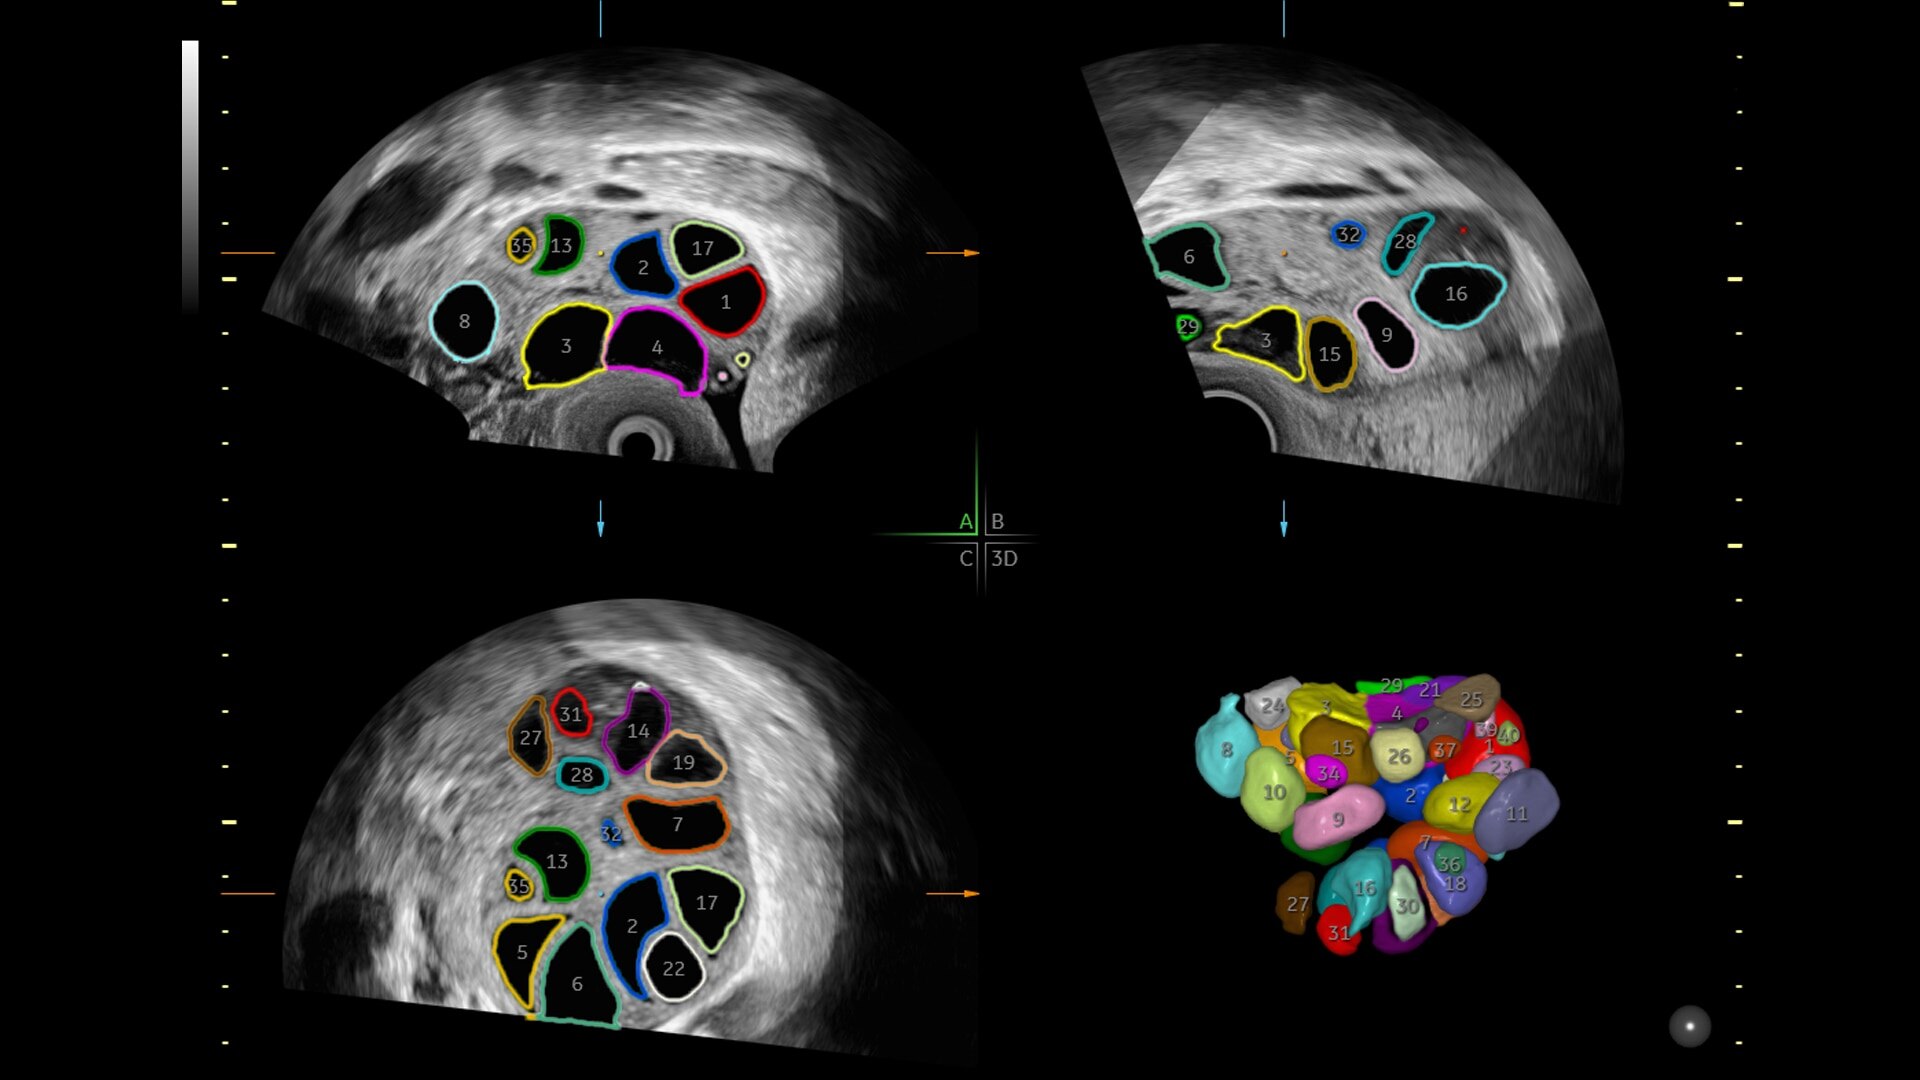

81%

SonoCNS reduces brain assessment exam time by 81%

Reduce keystrokes by 83% with 3D Spine Trace

88%